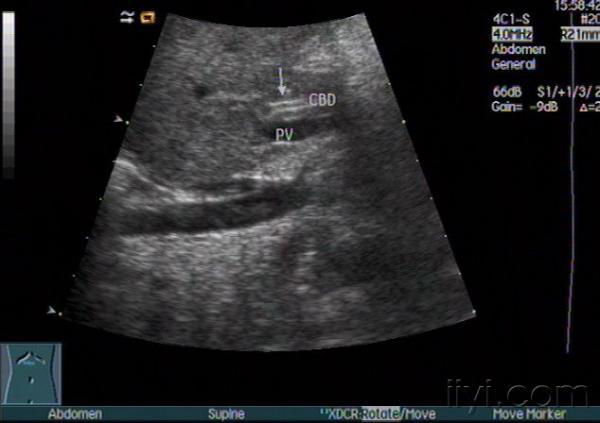

胆道闭锁?

小儿黄疸,是胆道闭锁吗??

太难了,本身就很细了,追踪下去难度很大的,而且探头稍微歪曲就有可能看错。不知此病例进一步检查确诊了没有?

图像没有胆道闭锁的征象啊!越来越不易啊